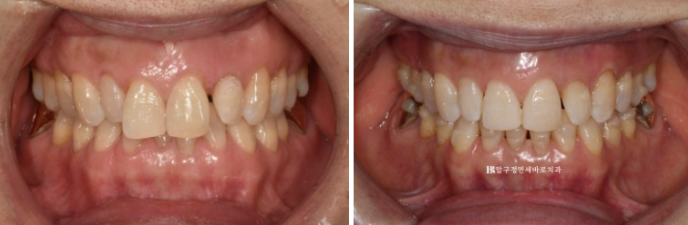

23.09~24.03

The alignment was well established.

24.08

Do you see the space on both sides of the peg lateral tooth?

The intended space for restoring the tooth size was successfully created.

After waiting 10 days for the no-prep laminate veneers, Gelami, to be fabricated, they were finally attached to the upper front eight teeth.

If teeth whitening is done right before attaching Gelami, the original yellowish tooth color can be minimized from showing through.

This patient also had teeth whitening right before Gelami was attached to lighten the base color.

To match the patient’s desire for naturalness, the tooth shapes were designed to exclude artificial elements as much as possible.

Here is a comparison of the before-treatment and after-treatment photos, including Gelami.

23.09~24.08

Who would think this patient is in their 50s?

The teeth and smile look like they’re in their 20s, right?